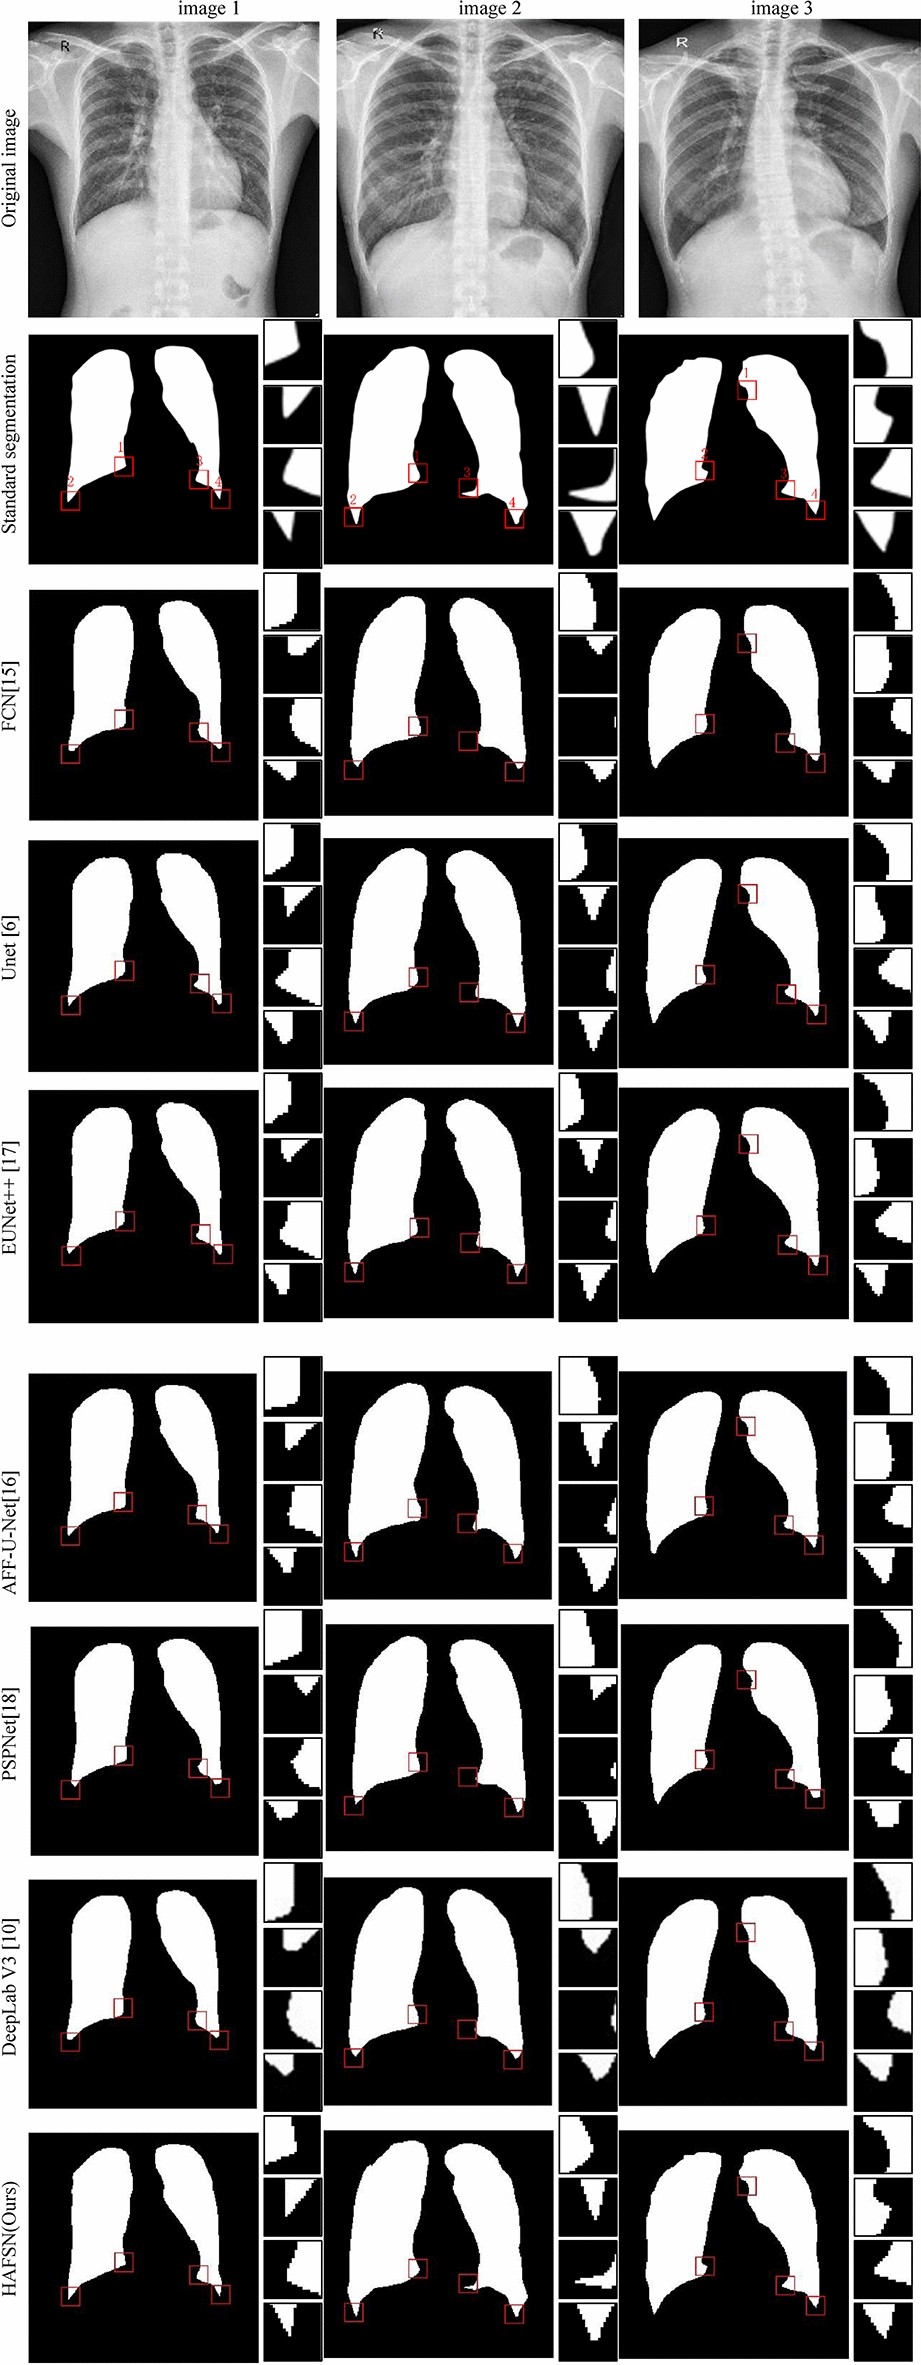

Fig. 9

Semantic segmentation effect diagram.